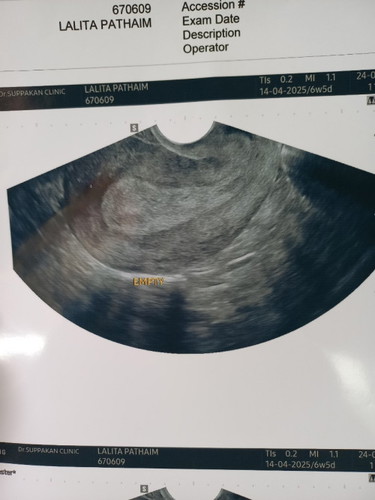

สอบถามบ้านไหนเป็นบางครั้ง ท้อง 7 week มีเลือดออกเหมือนประจำเดือน ไปหาหมอซาวด์ไม่เจออะไรเลย หมอแนะนำให้ไปซาวด์อีกครั้ง ตอน 10 week วิตกกังกลมากกลัวน้องไม่ปลอดภัย แม่ๆเจอน้องตอนกี่วีคกันบ้างค่ะ #ขอบคุณล่วงหน้าสำหรับความคิดเห็นค่ะ

กำลังตั้งครรภ์